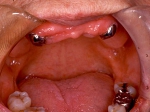

上部装着後のレントゲン像上部装着後のレントゲン像上部装着後のレントゲン像 術前口腔内写真術前口腔内写真術前口腔内写真 術後口腔内写真術後口腔内写真術後口腔内写真、食事がおいしくなったと非常に満足されている。